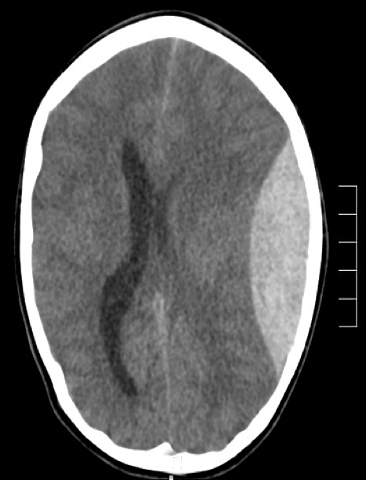

Sulcus - sestern

Concave esccentric in shape, ++++ hypo dense